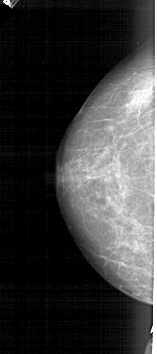

A_1489_1.RIGHT_MLO

RIGHT_MLO LINES 5491 PIXELS_PER_LINE 2116 BITS_PER_PIXEL 12 RESOLUTION 43.5 OVERLAY